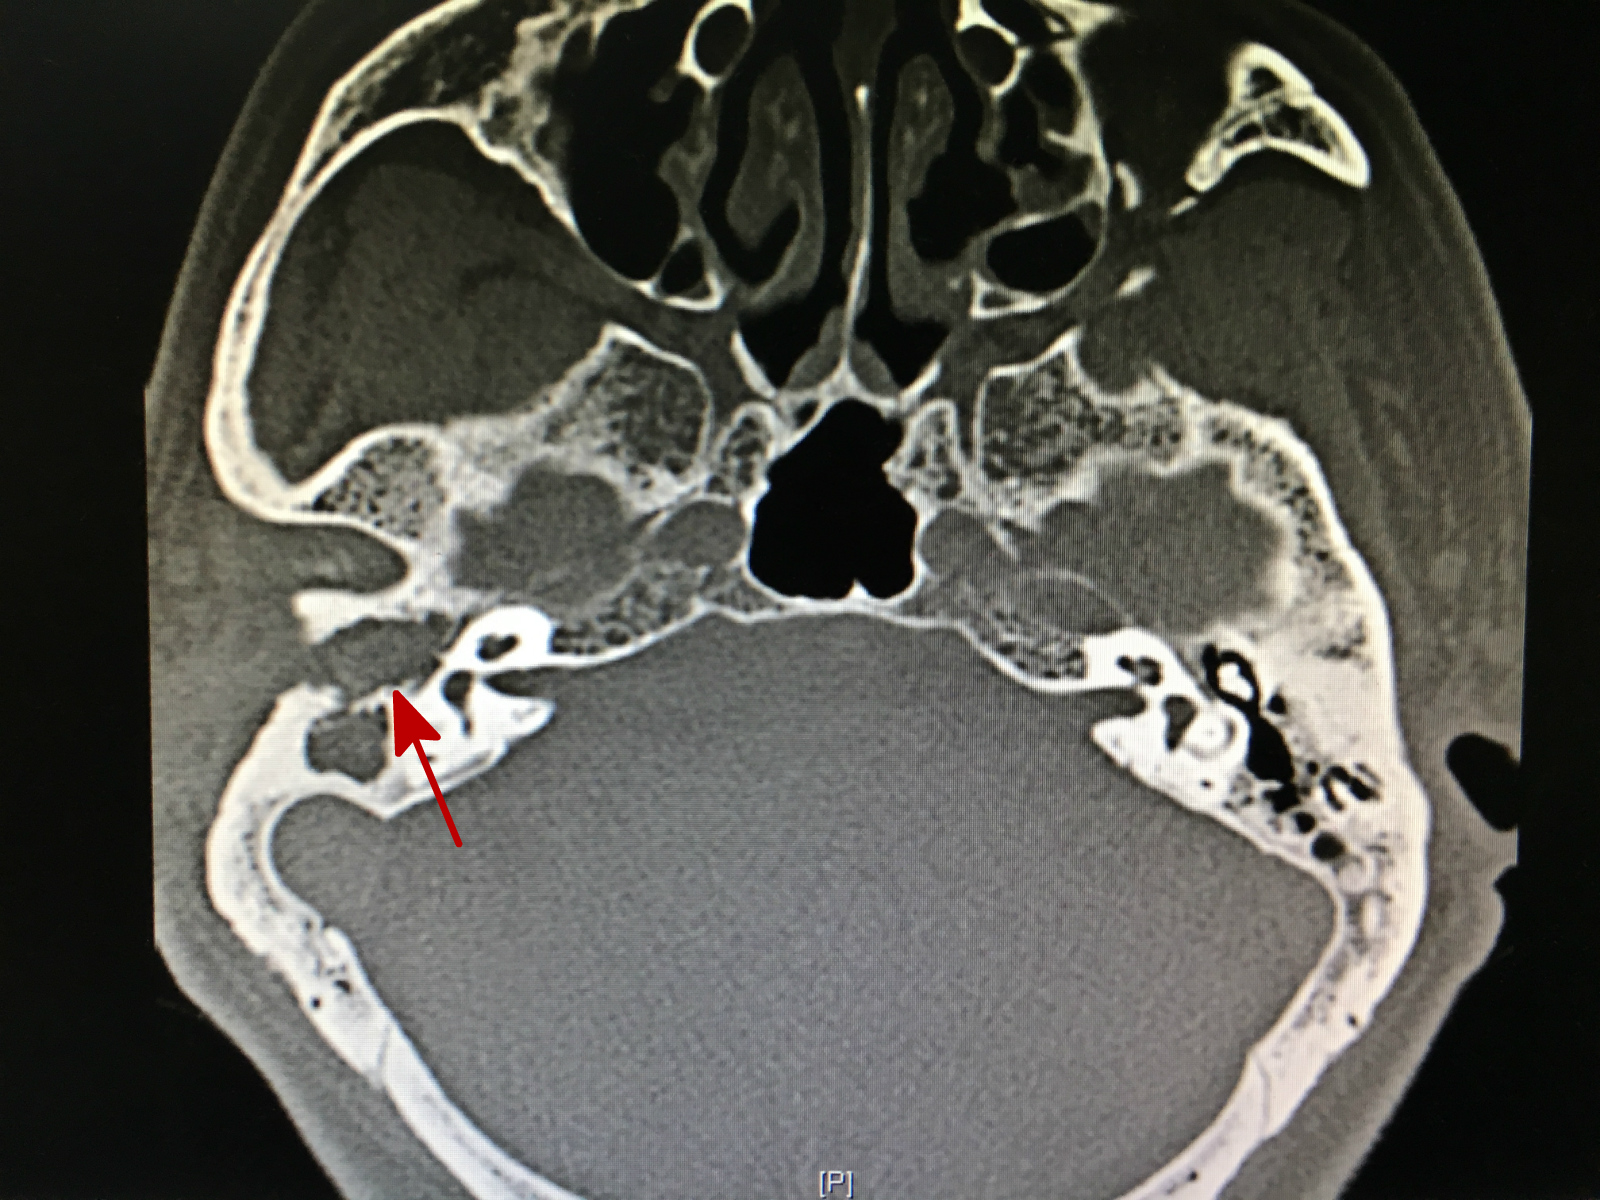

图中箭头所指灰色部分为中耳胆脂瘤

由于刘爷爷年事已高,心肺功能都有些问题,全麻手术的风险很大,伊海金副主任医师和团队经过审慎的评估,于8月25日为他做了手术。在麻醉医师的配合下,伊海金将胆脂瘤从颅底硬膜以及面神经表面剥离,消除了老人并发面瘫及颅内感染的风险,手术过程很顺利。刘爷爷说“仿佛睡了一觉,一觉醒来已在病房,没有感觉到任何疼痛”。手术不仅清除了病变,而且帮助患者恢复了听小骨之间的连接,重建了听力。目前刘爷爷在家休养,耳疼、头痛及眩晕的症状已经完全消失,听力也比术前有所提高。